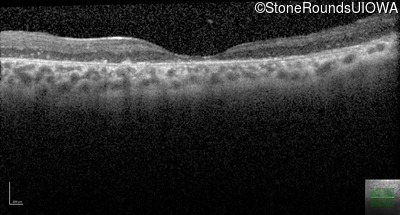

Optical Coherence Tomography - Right - 10/200

Exemplar / OCT Stack